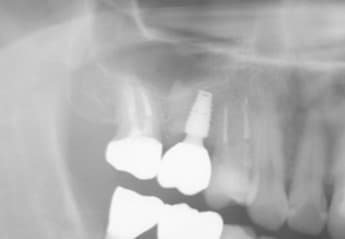

レントゲン画像⇩

このケースは、インプラントを埋入するための骨が不足していた為、はじめ上顎洞への骨造りを検討しました。

しかし、できる限り大掛かりな外科を回避するため、先ずは歯を抜いた部分へのGBR(骨造り)を行い、垂直的かつ水平的な骨の量を増やしました。

骨が出来上がってから、CT撮影を行い、解析画像からインプラントを埋入できる骨の距離を正確に計測し、ここしかない!というピンポイントで埋入する部位を決め、専用のサージカルガイドを製作してオペを行っていきました。(インプラントの先端は上顎洞ギリギリの位置に設置。)

結果、上顎洞挙上術という大掛かりな外科処置を回避することができました。

この埋入方法は、高機能のCTや解析診断ソフト、そして正確なサージカルガイド(簡易的なものは、精度に不安があります。)がなければ、なかなか難しい方法です。

フリーハンドでは、狙った方向にドリルを進めていき、上顎洞の手前でピタリと止めることはなかなか難しく、尚且つインプラント自体を完全に骨の中に入るための位置は、1ヶ所しか無かったので、ガイドのメッリトを最大限利用できたケースだった思います。